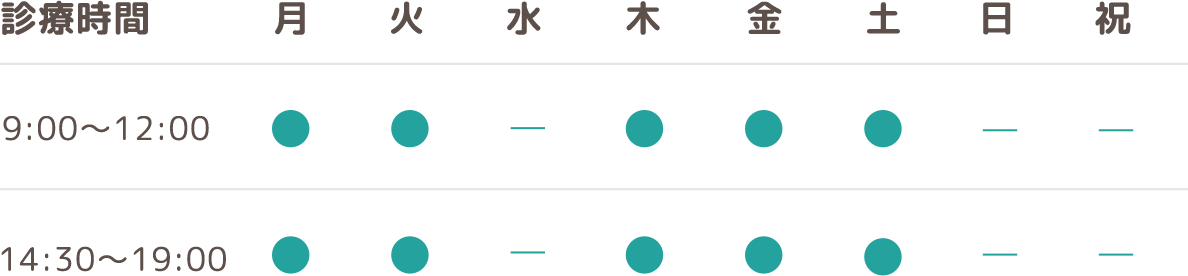

いずみ歯科矯正歯科医院では口腔機能を重視した矯正治療を心がけています。

口腔機能には咀嚼、嚥下、発音、呼吸などがありますが、これらの機能は子供の時期から大人と同じ能力を持っているわけでは無く、習慣性随意運動といって年月を重ねて習得していきます。

また、特に受け口(下顎前突)は上下の咬み合わせが通常と逆になるため筋肉や骨の形が通常と変わってきます。

そのため受け口は将来の顔貌にも影響を与える為に早期の治療が治療効果を発揮する症例と言えます。

7歳 女子の受け口の骨格です。

同じ人の1年後の骨格です。

小学校低学年の治療であれば、この変化は普通に起こる変化です。

骨格のことからも受け口は早期治療の効果が得られやすいです。

しかしながら20歳位まで受け口を放置するとその骨格は

このように変化します。

この変化は反対に咬むことに骨格が適応したことによります。